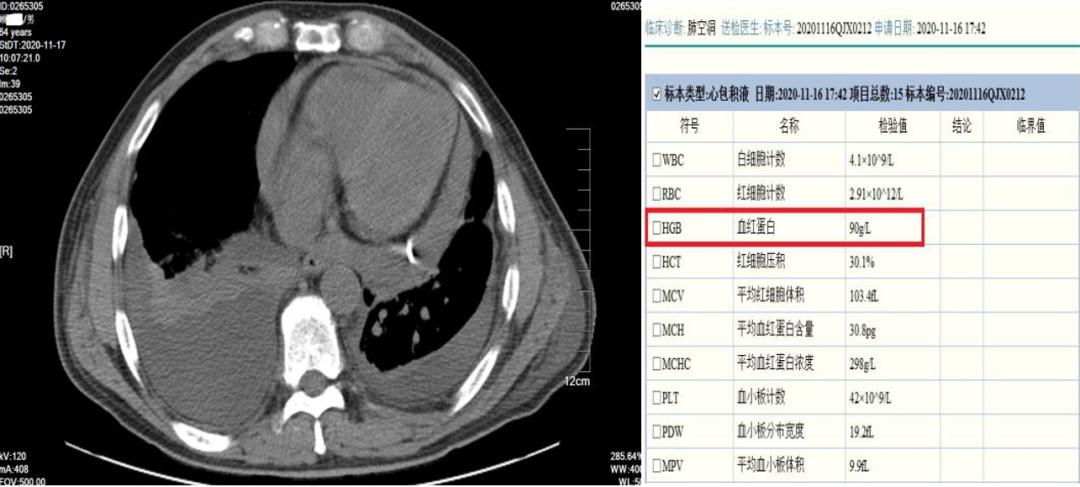

引流胸水及心包积液,血常规检测发现患者血红蛋白达到90g/l.